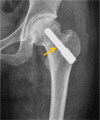

Steroid-associated osteonecrosis (SAON) is a common orthopaedic problem caused by administration of corticosteroids prescribed for many nonorthopaedic medical conditions. We summarised different pathophysiologies of SAON which have adverse effects on multiple systems such as bone marrow stem cells (BMSCs) pool, bone matrix, cell apoptosis, lipid metabolism, and angiogenesis. Different animal models were introduced to mimic the pathophysiology of SAON and for testing the efficacy of both prevention and treatment effects of various chemical drugs, biological, and physical therapies. According to the classification of SAON, several prevention and treatment methods are applied at the different stages of SAON. For the current period, Chinese herbs may also have the potential to prevent the occurrence of SAON. In the future, genetic analysis might also be helpful to effectively predict the development of ON and provide information for personalised prevention and treatment of patients with SAON.